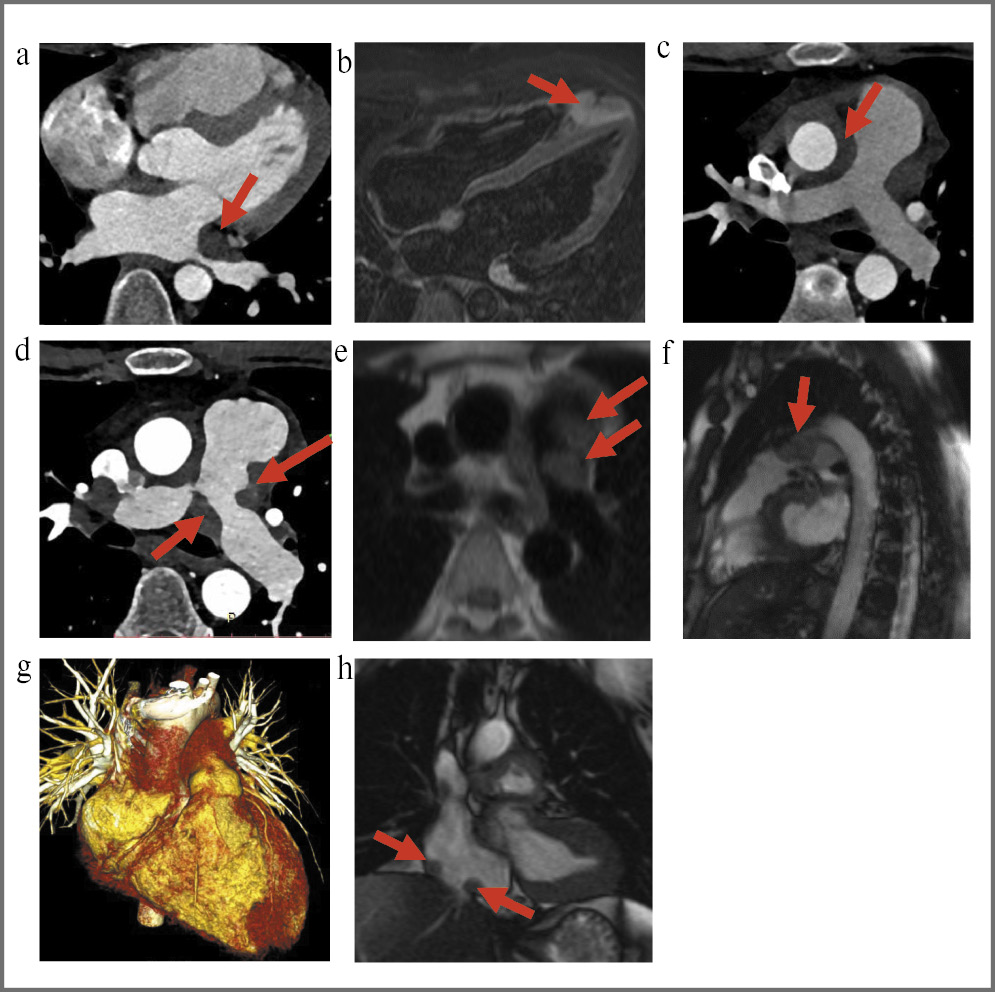

Через 6 мес на фоне удовлетворительного самочувствия пациента при контрольных КТ- (компьютерная томография) и МРТ-исследованиях отмечено увеличение размеров образования в области верхушки ПЖ, появление мягкотканых инфильтратов, муфтообразно окутывающих аорту в восходящем отделе, легочную артерию (ЛА) и ее ветви, верхнюю полую вену, проксимальную часть правой коронарной артерии и ствол левой коронарной артерии (ЛКА). Дистальная часть передней межжелудочковой ветви ЛКА частично располагалась в толще инфильтрата. Также выявлялось образование в области левого предсердия (ЛП), деформирующее полость ЛП (рис. 1).

Рис. 1. Локализации инфильтратов в области сердца и крупных сосудов у пациента К. (данные КТ и МРТ): а – инфильтрат в области ЛП со сдавлением легочных вен (КТ, 2020 г.); b – округлый инфильтрат в области верхушки ПЖ (МРТ, 2018 г.); с – парааортальный инфильтрат (КТ, 2018 г.); d–f – инфильтраты в области ЛА с сужением просвета ЛА (КТ и МРТ, 2020 г.); g – трехмерная реконструкция КТ-изображений в 2018 г. (красным цветом отображены зоны специфической инфильтрации); h – инфильтраты в области устья нижней полой вены (МРТ, 2020 г.).